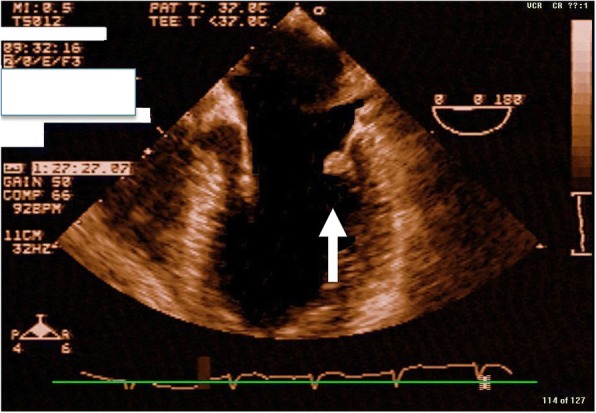

Fig. 2.

Transesophageal echocardiogram depicting mitral valve mass

A 32-year-old, previously healthy, African American man presented to an emergency department 45 minutes after the acute onset of left facial droop and right-sided weakness (Fig. 1). A thorough history confirmed an episode 1-week prior, during which he developed sudden onset of dizziness associated with nausea and vomiting that resolved within hours. He denied any past medical or surgical history and was taking no medications. He has no family history of tumors. In the emergency room, his vital signs were within normal limits. His physical examination was significant for a left facial droop and right hemiparesis. Auscultation of his chest revealed a regular rate and rhythm with no appreciable murmur. No additional significant findings were noted. Stroke protocol was initiated. A chest X-ray was normal and an electrocardiogram showed normal sinus rhythm. A head computed tomography (CT) scan was negative for signs of intracranial hemorrhage. He was subsequently started on tissue plasminogen activator (tPA) therapy. Magnetic resonance imaging (MRI) of his brain demonstrated a right basal ganglia infarct and an old left cerebral infarct. A carotid ultrasound was negative. TTE demonstrated a 1 cm by 1 cm mass on the posterior leaflet of the mitral valve with a moderate mitral regurgitation In addition, TTE revealed a questionable mass on the left coronary cusp of the aortic valve. These findings were confirmed with TEE (Fig. 2), which verified no sign of endocarditis and no atrial septal defect. A complete hypercoagulable workup was negative. Stroke protocol continued with the working diagnosis of cerebrovascular accident secondary to emboli from the mitral valve mass. Within 24 hours, he regained function of the right side of his body and had complete resolution of symptoms. He was diagnosed as having transient ischemic attack (TIA) and discussion was undertaken regarding surgical excision of his mitral valve mass.